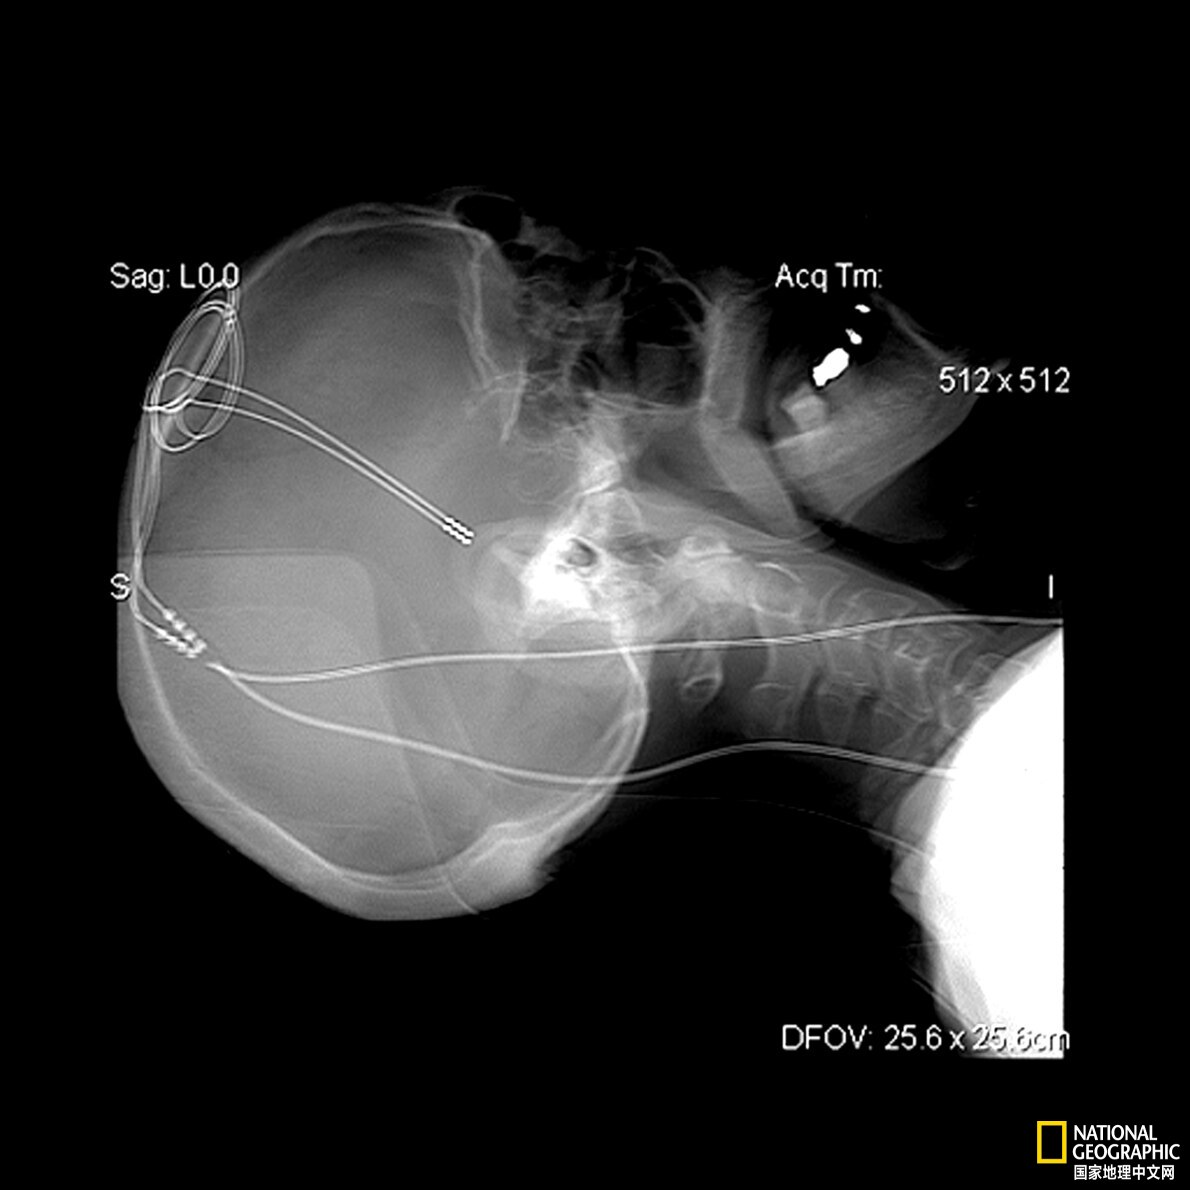

几十年来,医生已证明,可以利用脑深部电刺激治疗癫痫或帕金森病患者。脑深部电刺激是指通过手术,在大脑深处植入电极,从而用电流刺激特定的神经元。生物学家、计算机科学家Michael Levin说,脑深部电刺激和迷走神经刺激“很好地应用了”生物医学。“我想让人们知道,这只是冰山一角。”供图:SCIENCE HISTORY IMAGES, ALAMY STOCK PHOTO

在治疗帕金森患者时,医生会把一个电极插入黑质,像起搏器一样发送周期性电脉冲,刺激剩下的神经元释放比平常更多的多巴胺,以弥补损失,帮助缓解颤抖等症状。供图:ALAMY STOCK PHOTO

帕金森病会攻击特定的神经元群体,它们负责在大脑中的一小部分(即“黑质”)产生神经递质多巴胺。随着这些神经元死亡,多巴胺减少,从而产生帕金森病症状,比如颤抖。在这片区域植入电极,像起搏器一样发送周期性电脉冲,可以刺激剩下的神经元释放比平常更多的多巴胺,以弥补损失,帮助缓解症状。